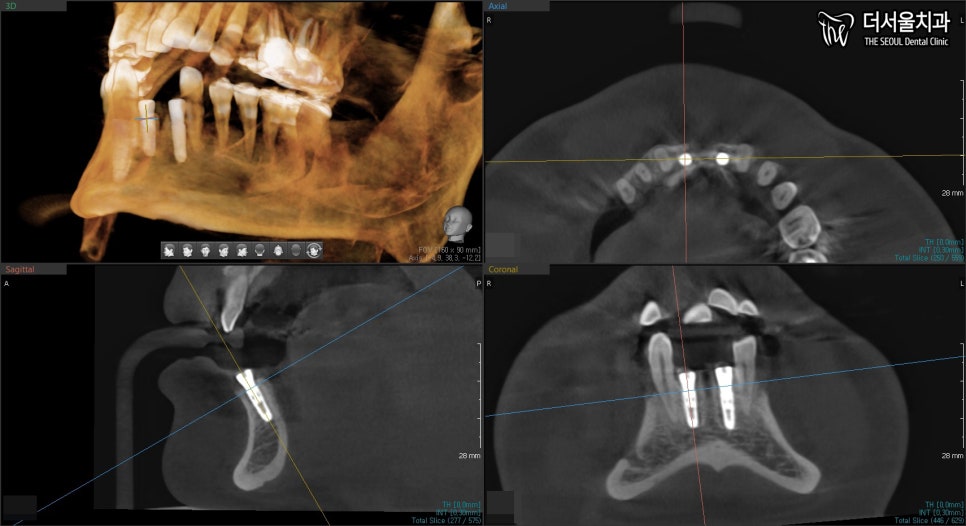

4. CT & 네비게이션 분석

충분히 회복 기간을 가지고

46, 47번 위치에 임플란트 수술을 계획합니다.

이때, 네비게이션 가이드를 이용하여

어떤 각으로 심으면 좋을지,

주의할 점은 무엇인지 확인합니다.

이후, 주의할 점에 맞춰 픽스처를 심습니다.

그리고 CT를 찍어서

식립 위치와 각이 잘 맞는지

꼼꼼히 확인합니다.

올바로 잘 심어졌네요. ^^